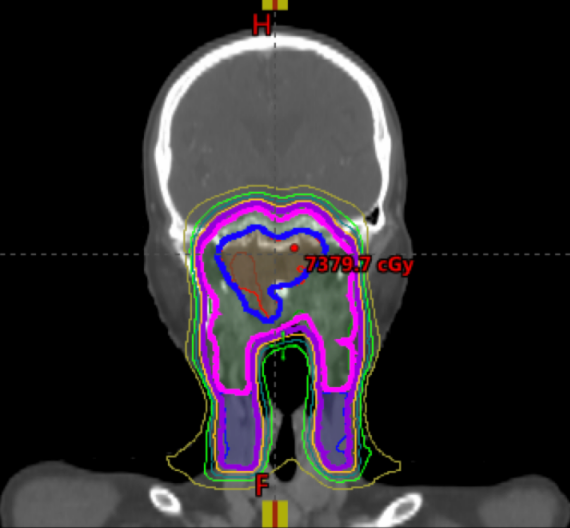

*某鼻咽患者应用TOMO技术,可以将剂量(蓝色)、高危剂量(紫红色)、低危剂量(紫色)完全和医生制定的照射范围适形。

放疗:精准诊治,显著降低副作用 所有患者均使用先进放疗技术,95%患者会应用旋转调强(VMAT)和螺旋断层调强(TOMO),相比起传统的精准放疗IMRT技术,进一步显著优化了颈部淋巴结的放疗照射区域;通过精准的影像学分析,缩小了放疗靶区,减少了对正常组织的辐射。

这一优化不仅提高了肿瘤控制率,还大幅降低了副作用,如口干、颈部皮肤损伤、吞咽困难等,显著提升了患者的生活质量。几乎所有患者在治疗后1年内不再明显感受到不适。